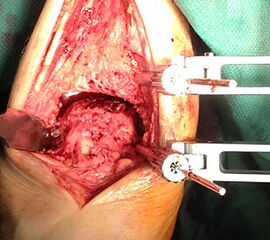

Kapsulotomie und Synovialektomie. Entknorpeln der Gelenkflächen bis knapp in den subchondralen Raum. Mit Kuretten, gebogenem Meißel, oszillierender Säge und/oder hochtourigen Fräsen Entknorpeln der tibialen, fibularen und tibialen Gelenkfläche und Abtragung von knöchernen Anbauten (Abb. 3). Die Präparation entlang der vorgegebenen Kontur des Talus und der Tibia bietet den Vorteil eines geringeren Längenverlustes gegenüber geraden Sägeschnitten. Der anteriore Zugang bietet insbesondere bei Verwendung eines Arthrodese Spreizers eine gute Übersicht in die anterioren Kompartimente. Der antero-laterale transfibuläre Zugang ergibt eine hervorragende Übersicht, allerdings nicht auf das mediale tibio-talare Kompatiment.

Abbildung 3